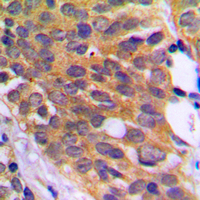

Anti-eEF2K (phospho Ser366) antibody used in IHC (Paraffin sections) (IHC-P). GTX32365

GTX32365 IHC-P Image

IHC-P analysis of formalin fixed human prostate cancer tissue section using GTX32365 eEF-2K (phospho Ser366) antibody.

Antigen retrieval : Heat mediated antigen retrieval with sodium citrate buffer (pH 6.0)